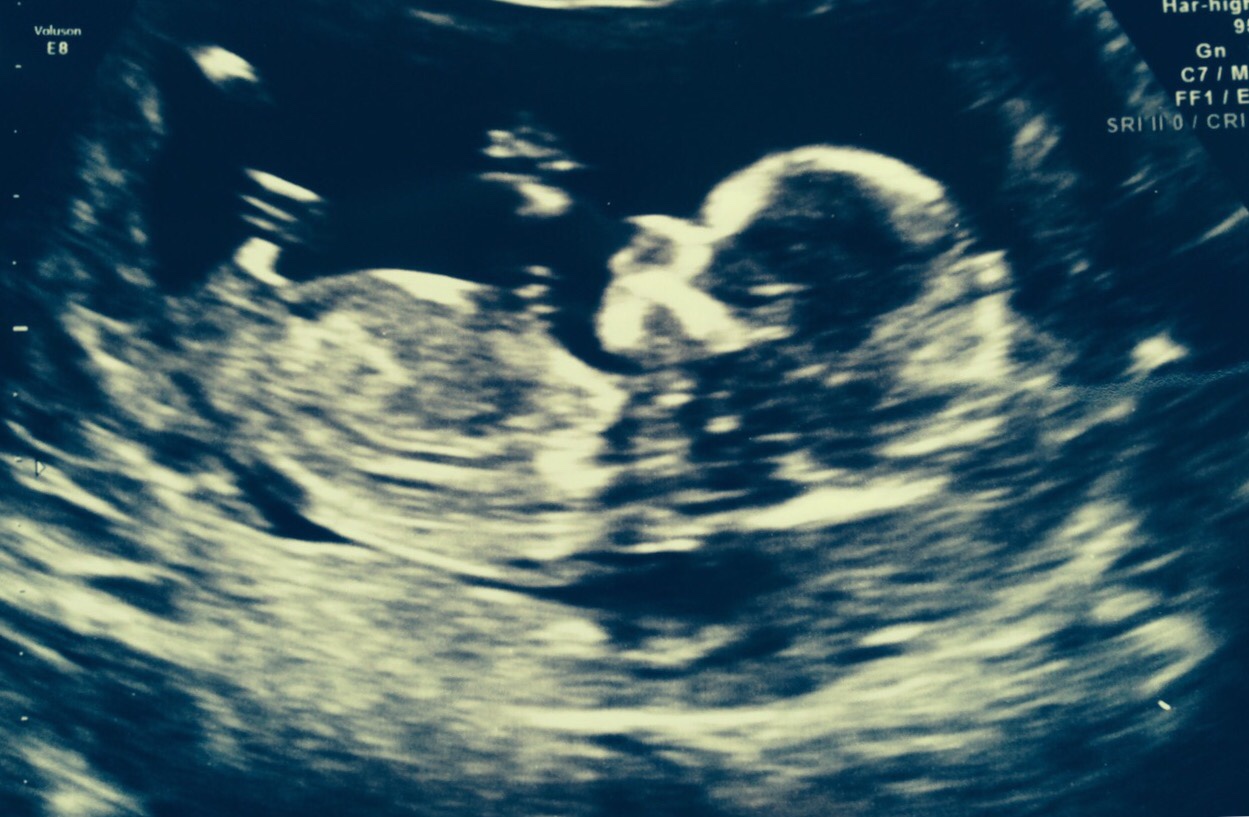

Here is a 12 week scan from a friend. I said I'd ask you girls for your opinions. Boy or girl? TIA

Never seen a nub like that before (and I have 3 boys!) but yeah if that bright spot that looks like a golf club is the nub then its gotta be a boy!

Skull looks boy too

IF that's the nub I think I'm seeing, I'm going to lean girl. FX!

Leaning boy

Just to confirm my friend had a boy.